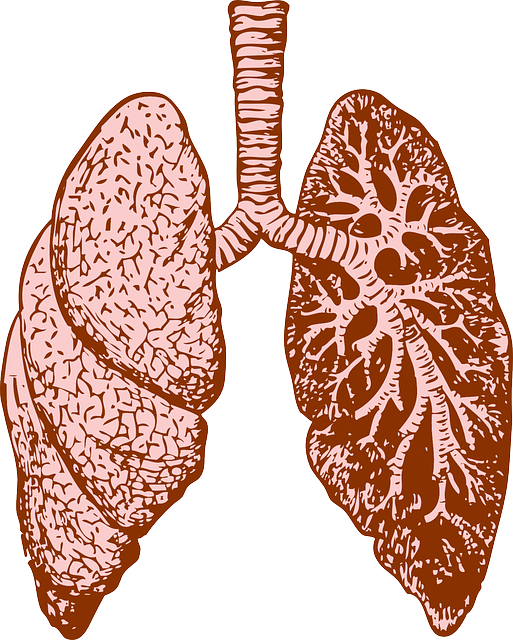

Sistema respiratorio:

Permite el ingreso de oxígeno al organismo y que a la vez pueda desechar el dióxido de carbono, el cual resulta nocivo para el cuerpo humano. Este proceso se realiza mediante la respiración y se transporta por la sangre.